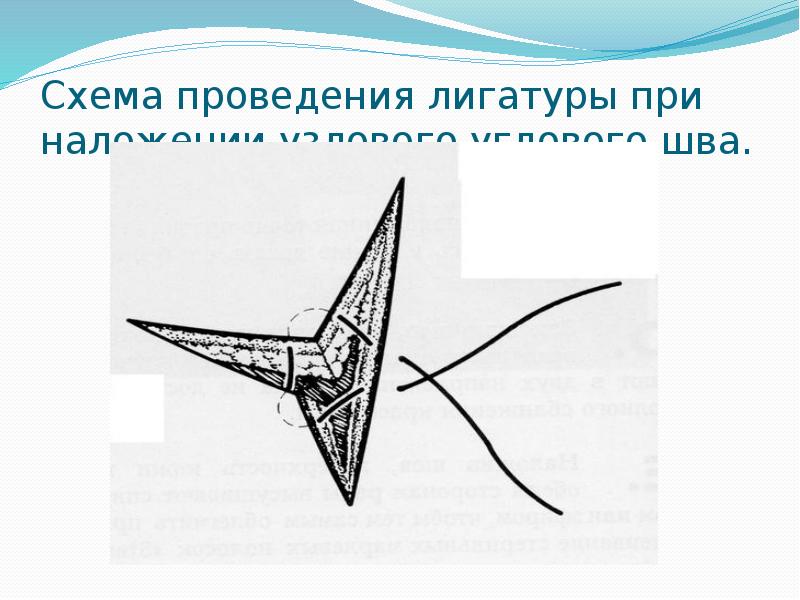

- 43. Схема проведения лигатуры при наложении узлового углового шва.